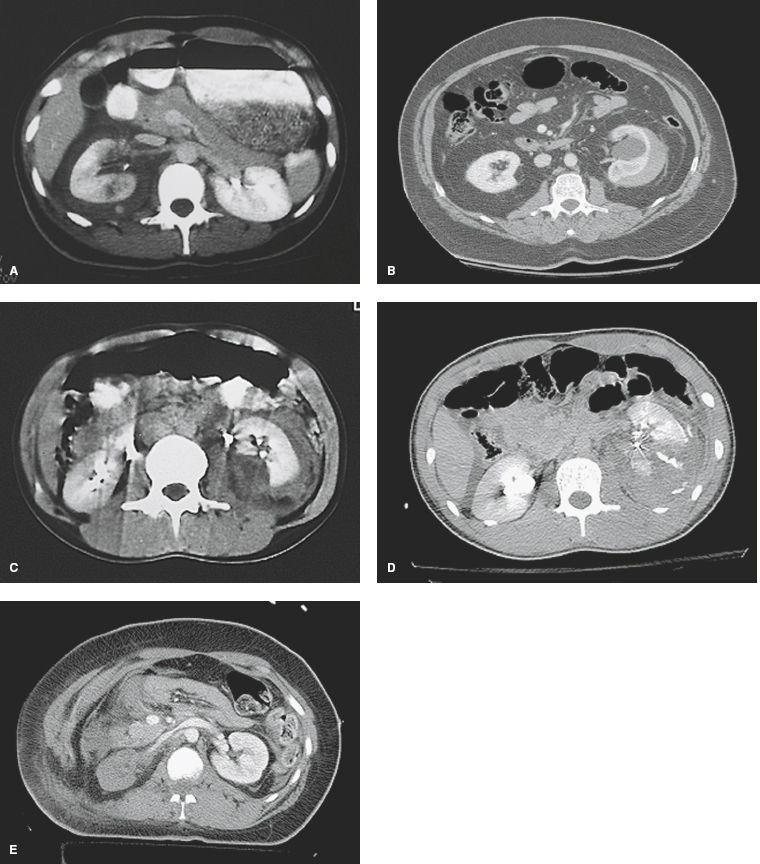

Figure 26-1. Grading of renal injury by computed tomography. A: Grade I, contusion; B: Grade II; C: Grade III; D: Grade IV, contrast extravasation; E: Grade V, devascularized.

2 Grade I and II injuries rarely require further management. The bulk of blunt grade III and nonvascular grade IV injuries should be managed nonoperatively, whereas only selected penetrating injuries in hemodynamically stable patients can be managed on observation protocols.11,12 Lacerations with associated collecting system injury (i.e., grade IV) can initially be managed with observation, although a subset of patients will require ureteral stenting due to persistent urinary extravasation. A proposed modification to the AAST OIS stratifies major renal lacerations into “high risk” and “low risk” based on the likelihood of intervention for hemodynamic instability.13 The CT imaging criteria of ICE, medial parenchymal laceration, and perirenal hematoma rim distance >3.5 cm have been validated to predict the need for intervention and may lead to further refinement in nonoperative management.14